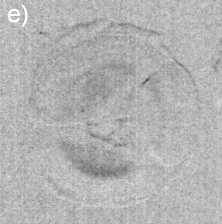

As summarized in Fig. 2, the image contrast criterions of DEI allows characterization of the scattering properties of the observed internal structures in the lenses. Diffuse-scattering, refraction, and absorption images were collected respectively at the tail (T), shoulder (S), and center (C) of the analyzer window, some good examples are shown in Fig. 3. In the former type of image, the amounts of diffuse-scattering around the internal structures are consistent to the type of scattering expected for an aggregation of tiny precipitates without a well defined boundary, as in Figs. 3(a) and 3(c). On the other hand, refraction images have shown aggregations with dense cores, Fig. 1(d) and 3(d), capable to refract X-rays in an opposite sense of air bubbles, arrow in Fig. 3(f). It indicates that the precipitates are denser than the lens tissue.

Dilute concentrations of precipitates without cores have also been observed, Figs. 3(e) and 3(f), as well as clinical cases of cataract with well-defined Y-sutures but with no distinct amounts of precipitates. In these cases, which correspond to 60% of the analyzed cases, there are significant scattering at the suture marks that can be generated either by local compaction of fiber cells or accumulation of precipitates along the marks, as for instance in Figs. 3(g) through 3(l). Refraction images show the extension of compaction areas while diffuse-scattering images can revel the presence or not of precipitates at the sutures. Absorption images (center of the analyzer window) provide essentially the same information of diffuse-scattering ones.